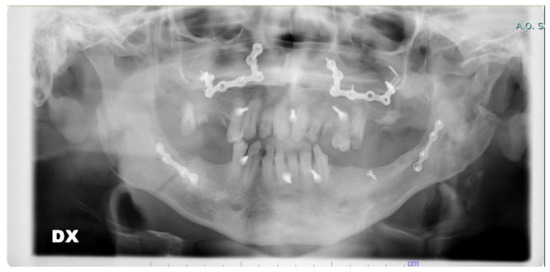

The procedure was adopted in one clinical case on a patient affected by a class III malocclusion with an associated open bite and right deviation of the mandible. The patient was a 27-year-old male already operated on 5 years prior for multiple fractures of the jaw after a car accident. Screws and plates from the previous operation were removed before new orthognathic surgery. Following our procedure, a high-definition skull CT scan was acquired and digital planning was performed. Evaluation of proper maxillary and mandibular segmentation and movements was performed considering class III, open bite, and asymmetry correction. Additionally, evaluation of gap or overlapping of the bone fragments at the osteotomy sites was acquired up to a final bone fragments positioning feasible in relation to anatomic and surgical technique limits. CAD/AM (Computer-Aided Design/Computer-Aided Manufacturing) surgical guides and custom-made fixation plates were acquired before surgery. In this special case, the standard plates were unable to be used for the particular conformation of the bones.

The surgery to which the patient was subjected required a BSSO and a Le Fort I osteotomy.

In the following figures, the medical images, orthopanoramic images (Figure 6 and Figure 7) before and after an orthognathic surgery, the implanting screws (Figure 8), and a digital reconstruction (Figure 9) are shown.

Operation was conducted without particular difficulties with the aid of the surgical guides and custom-made plates and screws fixation system. Surgical guides precisely fitted in the planned facial skeleton areas and pre-drilling holes precisely combined with custom-made plates holes resulting in proper jaw positioning and dental class I occlusion. Additionally, the amount of bone gap and overlapping at the osteotomy sites was restrained to an acceptable degree in relation to anatomic and surgical limits by proper planning combining main skeletal advancement for the upper jaw (5 mm) with a limited amount for mandibular set-back (3 mm) combined with left rotation of the lower midline up to precise fitting with the upper midline.

In this way, we had a small gap between the two mandibular segments at the BSSO sites easily managed at the fixation time during surgery, also preserving a correct condylar position in centric relation.

After cephalometric and occlusal evaluation, the result was considered fully satisfactory for the clinicians and for the patient.

Additionally, masticatory function was evaluated as absolutely satisfactory 6 months after surgery with good stability at one year after x-ray cephalometric and occlusal control. The post-operative TC and the one-year-after control TC showed that the hypothesized errors in applying the proposed methodology were lower than the maximum one (0.65 mm) and acceptable for the BSSO approach.

Figure 7. Post-operative view showing personalized CAD/CAM plates after the previously installed plates removal and orthognathic surgery class III correction.